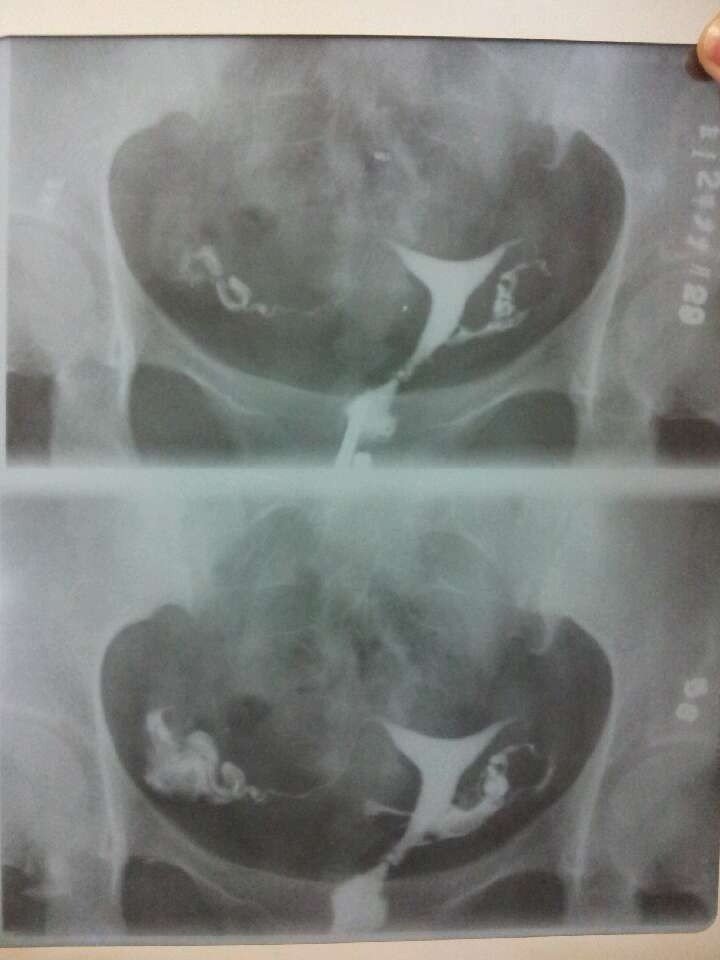

碘佛醇 输卵管造影 报告单 帮忙看看,跪求高手指点

患者信息:女 24岁 病情描述(发病时间、主要症状等):不孕检查输卵管造影想得到怎样的帮助:自己看不懂,想问问结果怎么样

输卵管通而不畅,右侧输卵管伞端粘连,会引起女性不孕或宫外孕,需要进行治疗,一般采用宫腹腔镜微创介入治疗。

可以做宫腔镜通开,通而不畅会引起宫外孕的,要引起重视